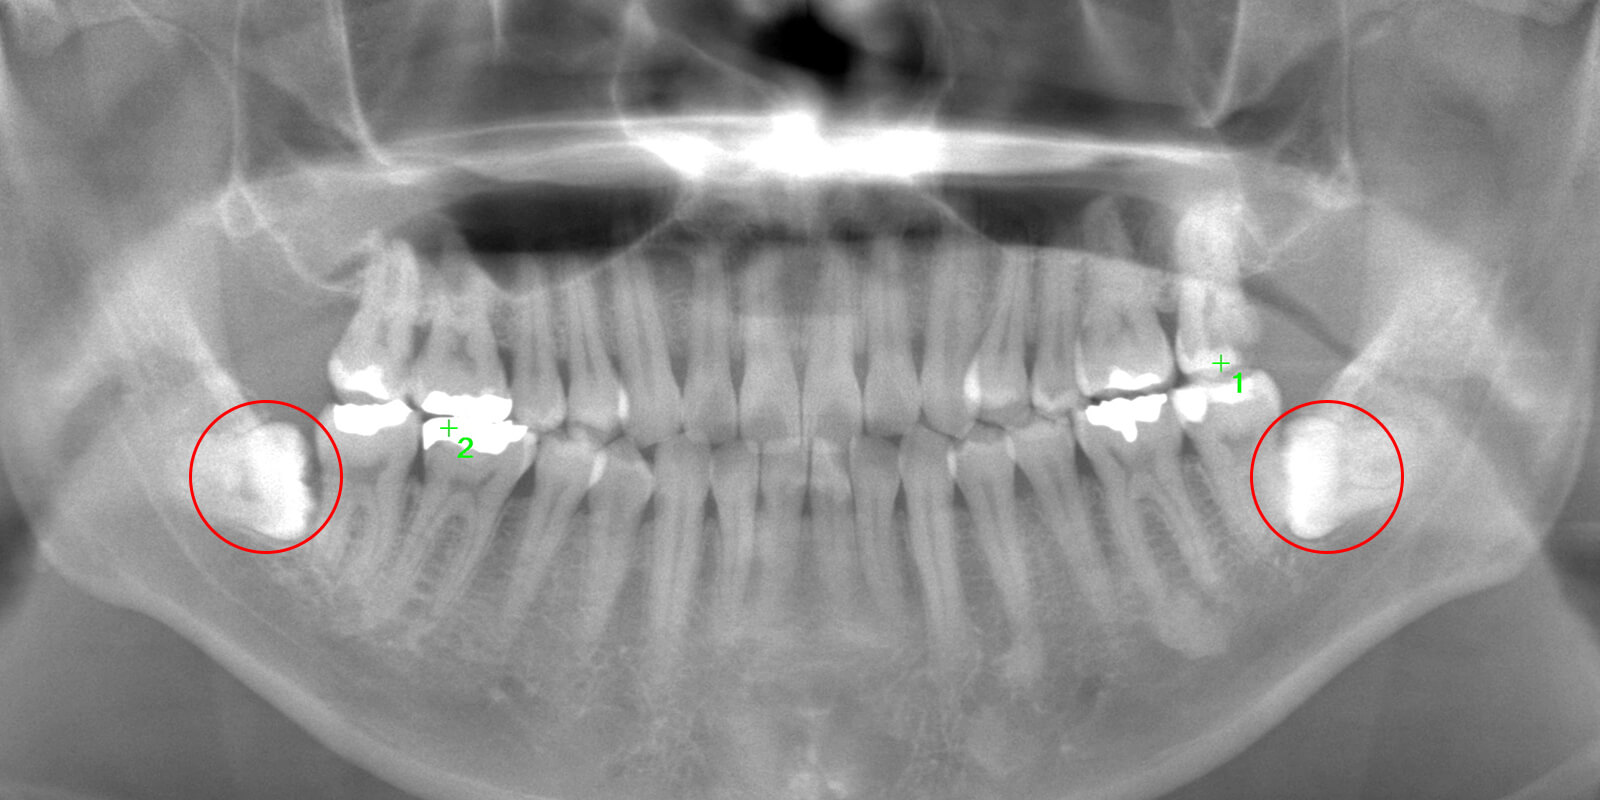

通常は「2次元」で撮影するレントゲンを使用して診断を行いますが、当院では「3次元」での撮影が可能なCTを用いてより詳細な診断を行います。

2次元と3次元では「見える範囲」が異なります。

下の画像は他の治療のケースですが、同じ部位を2次元レントゲン(左)、3次元のCT(右)で撮影したものです。

丸がついている部分が問題の生じている部分で、3次元ではしっかり黒い影が見えますが、2次元ではそれが確認できません。

簡単にまとめると、2次元レントゲンだけでは「問題が見落とされる」可能性があるということです。

歯科医療では、「見える」「見えない」が大きな違いを生みます。

当院では、しっかりとした視野を提供する3次元のCT装置を使って診断を行っています。